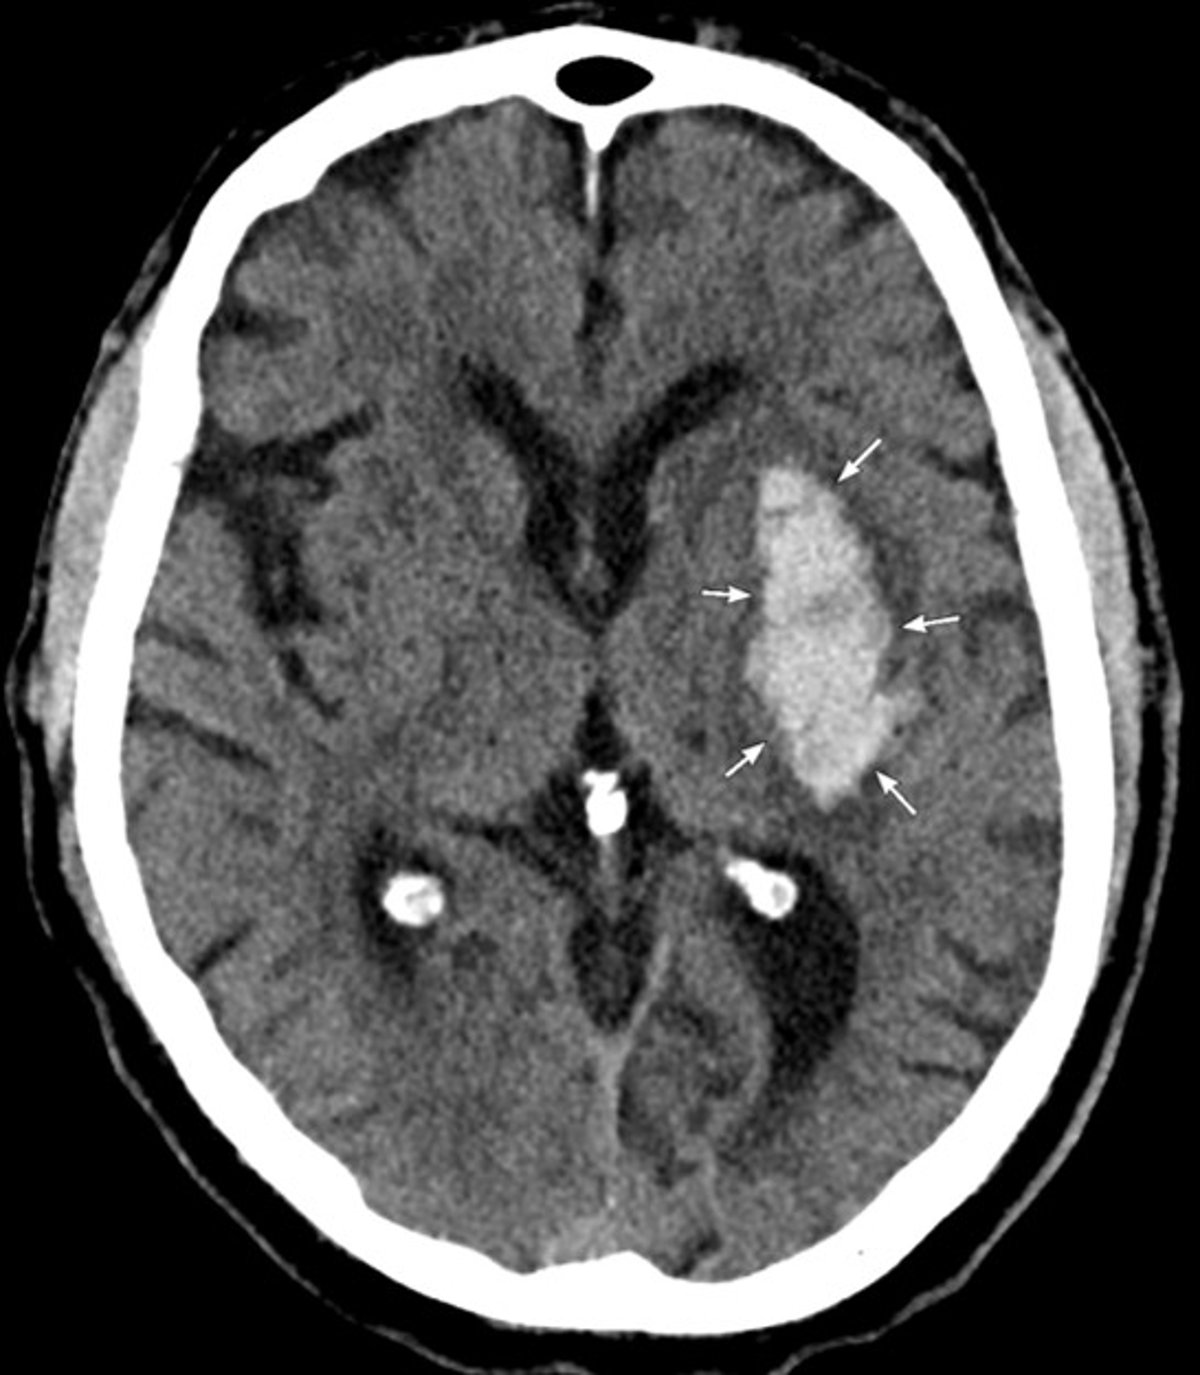

TC della testa

La TC mostra un'emorragia acuta nei gangli della base sinistra compatibile con un'emorragia ipertensiva intracerebrale.

Image courtesy of Mustafa Mafraji, MD.